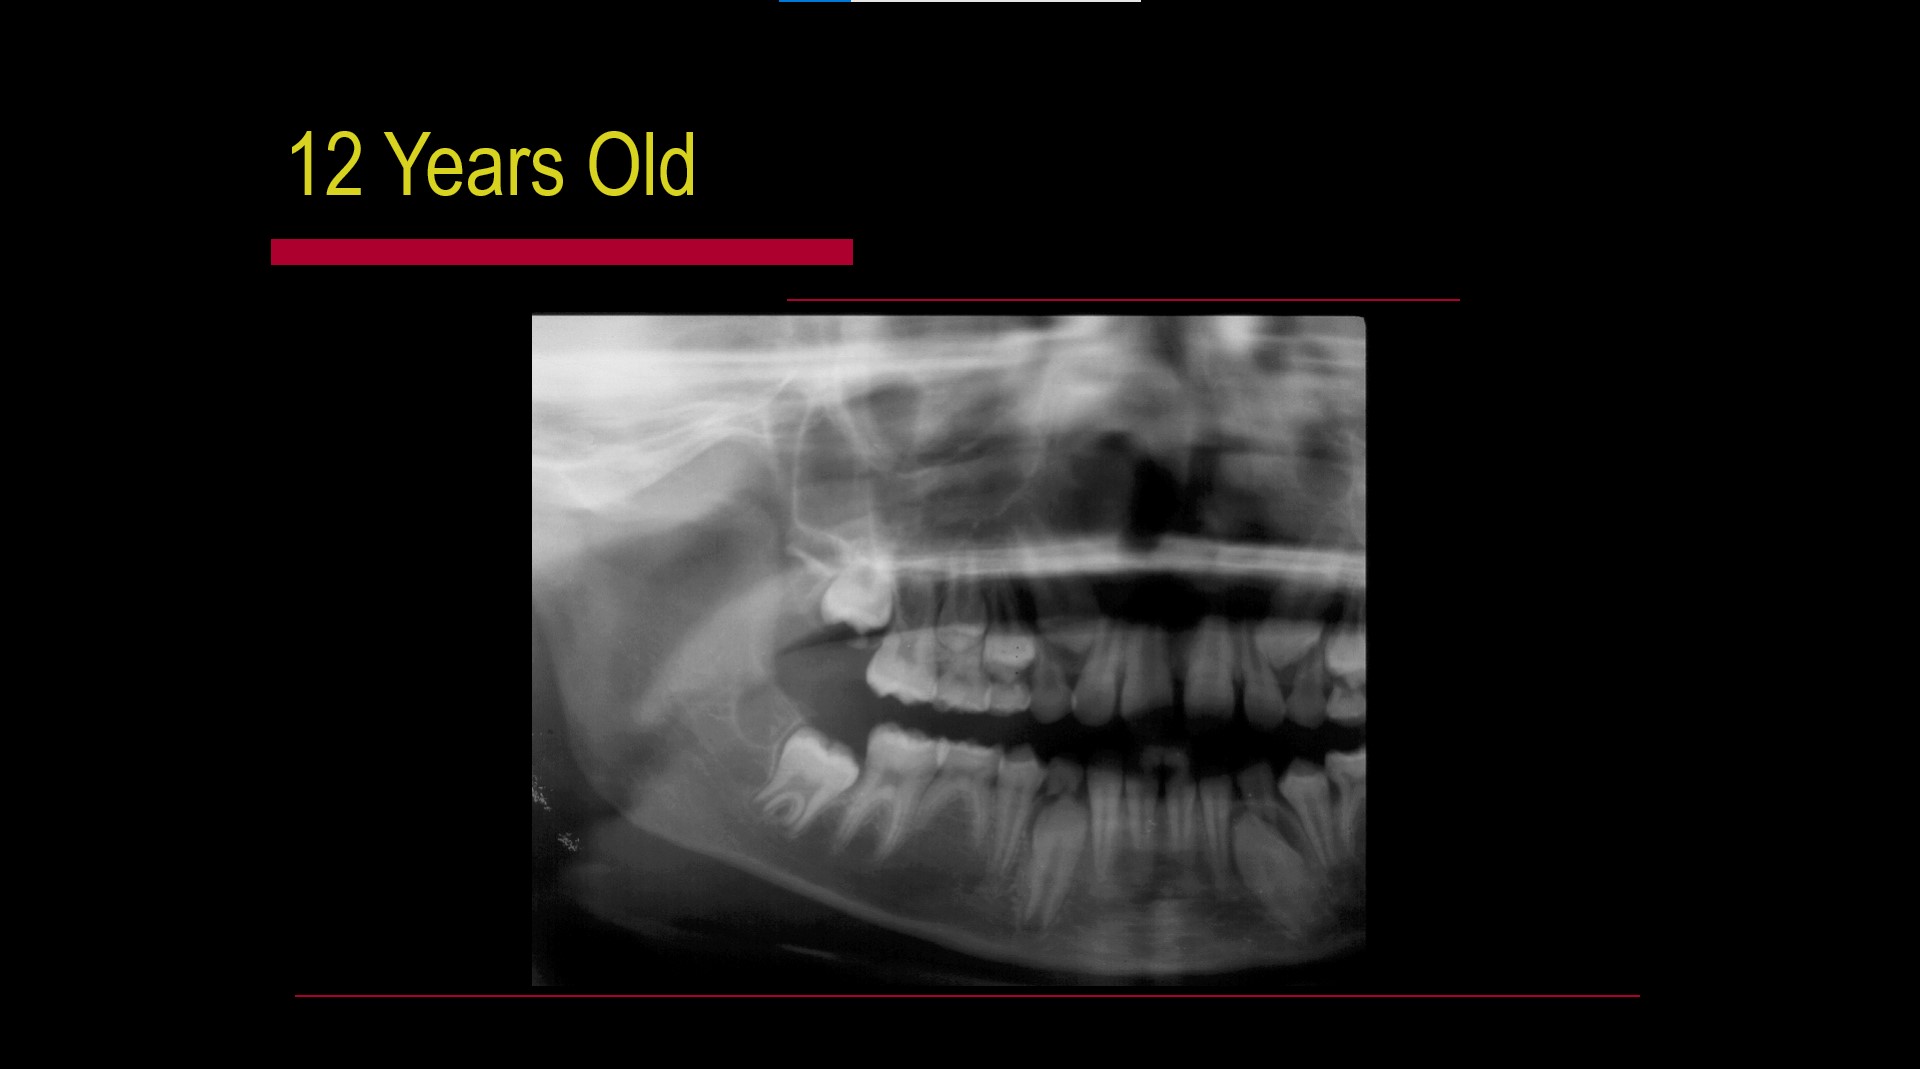

Impacted teeth